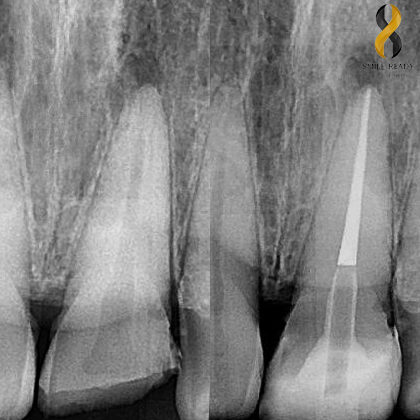

PERIAPICAL X-RAY

IDR 200.000 (Per Tooth)

Is taken to evaluate the periapical area of the tooth and surrounding bone.